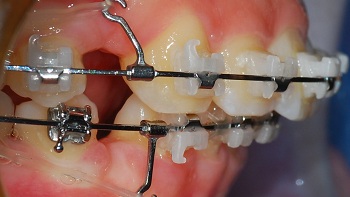

<측면 치아 사진>

정말 많이 들어갔죠?